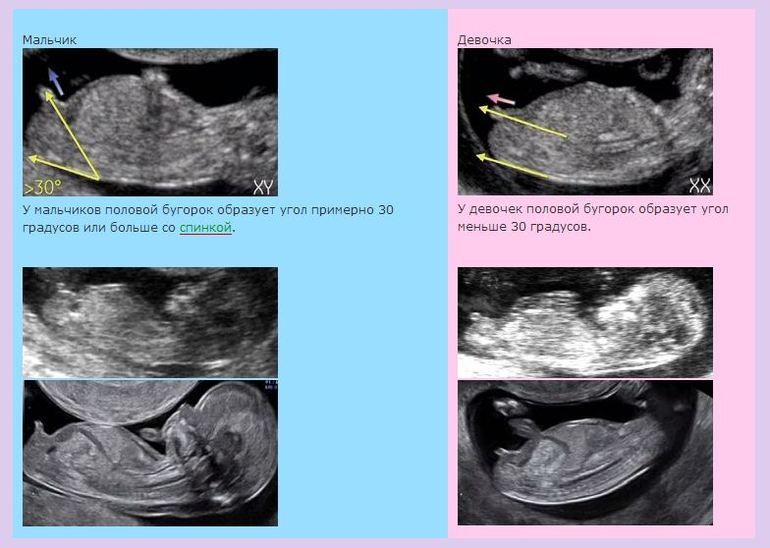

Лина, на таком сроке очень легко перепутать, потому что выглядят одинаково практически что мальчики, что девочки, и грамотный узист не будет предполагать, если не понимает. На вашем фото не видно... Надо, чтобы вот так выглядело))

Может, Вам переделать у другого специалиста? Либо подождать недель до 15-ти - там уж яснее будет.